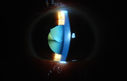

Silicone Oil in the Anterior Chamber1048 viewsPatient comes in for second opinion for retinal detachment in the left eye. VA is hand motion in the left eye. Poor view to look into the retina. Small silicone bubble at 12 o'clock superior in the anterior chamber. Surgery was not recommended due to the silicone oil in the left eye. 55555